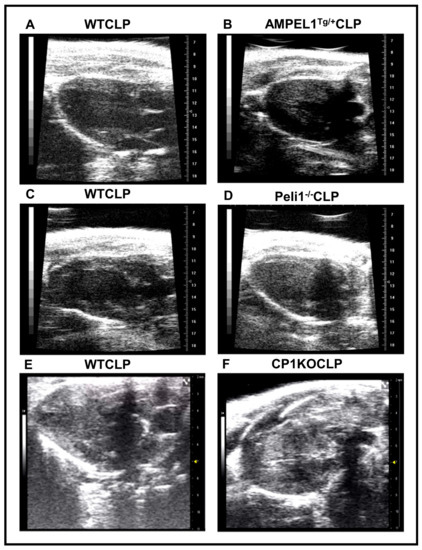

3.1. Overexpression of Cardiomyocyte-Specific Pellino-1 (AMPEL1Tg/+) Allows Preservation of Ejection Fraction and Other Echocardiographic Parameters following Severe Sepsis

3.2. Effect of Pellino-1 Global Knockout (Peli1−/−) and Cardiomyocyte-Specific Pellino-1 Knockout (CP1KO) Mice Subjected to Severe Sepsis on Cardiac Functions